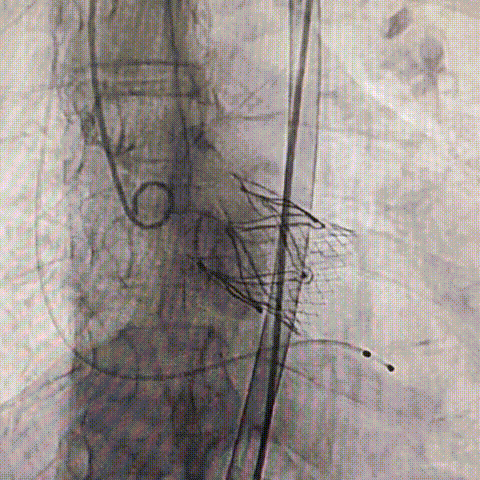

2026年伊始,TaurusTrio经导管主动脉瓣系统在复旦大学附属中山医院,浙江大学医学院附属第二医院,中国医学科学院阜外医院,首都医科大学附属北京安贞医院,四川大学华西医院等多家临床中心成功开展上市后全国首批植入。这不仅是TaurusTrio正式走向广泛临床应用的重要里程碑,更标志着中国单纯主动脉瓣反流介入治疗正式迈入了“心键合璧”的全新纪元。